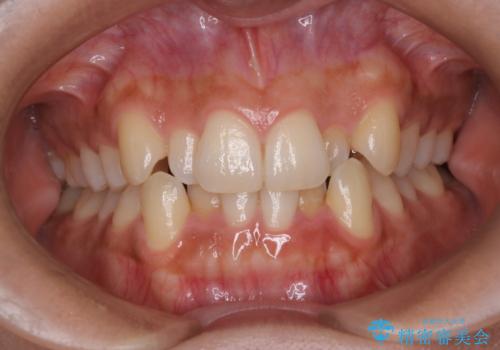

【抜歯インビザ】凸凹を綺麗になおしたい

担当医 河口智英